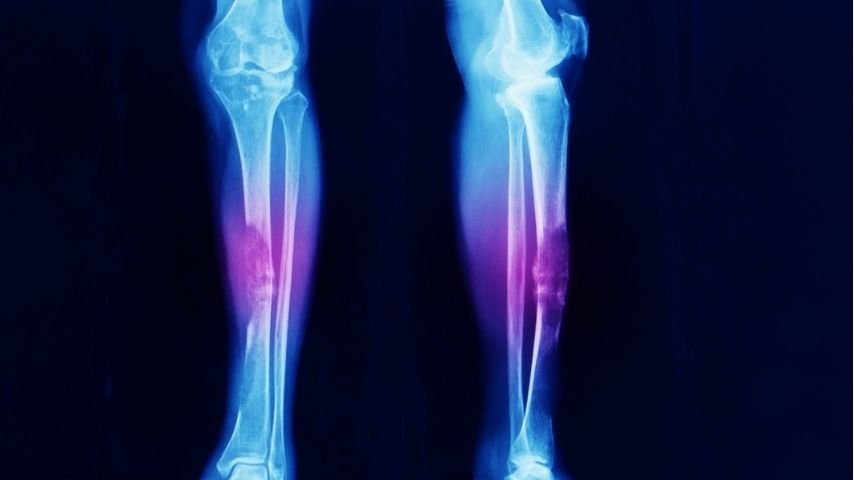

Bone sarcomas start inside the bone itself. They often affect long bones of the arms or legs, but they can also develop in the pelvis, spine, or ribs. Because bones provide structure and strength, tumors inside them behave differently from those in soft tissue.

Bone sarcomas are more likely to cause pain, swelling, or even fractures because they weaken the bone from within. Surgery must therefore address not only cancer removal but also the mechanical stability of the skeleton. This makes bone sarcoma surgery more complex and physically demanding in terms of reconstruction and recovery.